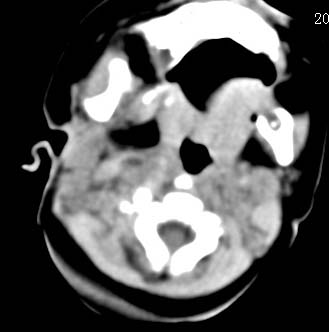

以下是引用zjzjr在2008-12-18 11:20:00的发言:[br]右颈部软组织肿块,性质待定(神经源性肿瘤等排),上下径较长,不太支持肿大淋巴结.